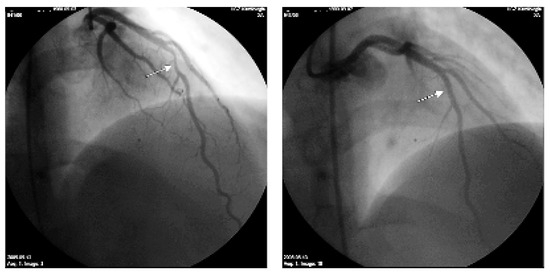

Akutes Koronarsyndrom im Alter von 25 Jahren?

by Barbara Kunz, Girish Ramteke, Philipp Herzog and Marco Roffi

Fallbeschreibung Ein 25jähriger gebürtiger Mazedonier wurde vom Hausarzt notfallmässig in die Notfallstation des UniversitätsSpitals eingewiesen [...] Full article